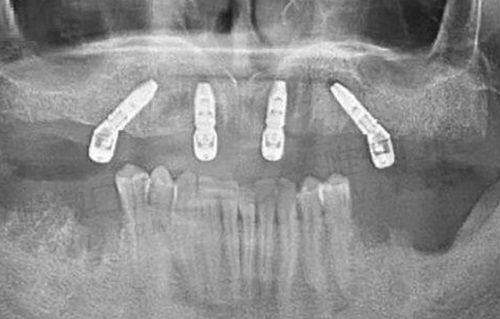

成都安玉牙种植医院之所以受欢迎,不光是靠老口碑和老医生,更关键的是它在技术上一直保持更新不掉队。医院采用的是全数字化导板种植系统,加上3D CT影像技术、术前模拟设计,基本做到了“毫米级定位”。这意味着植牙时能精细避开神经、血管,减少创伤,同时大幅缩短术后修复时间。

微创即刻种植术,是该院特别主打的项目之一。这项技术可以做到拔牙和种植“一气呵成”,部分患者当天种牙当天戴牙,再也不需要漫长等待。对于经济能力强的患者,医院还提供ITI、诺贝尔、瑞锆等高端品牌种植方案。

除了单颗、多颗牙种植外,安玉牙种植医院在“全口无牙颌重建”方面也下足了功夫。不管是老年人因为脱落、磨损造成的大面积缺牙,还是因意外导致的复杂牙齿缺失,这里都能提供定制化的种植方案。